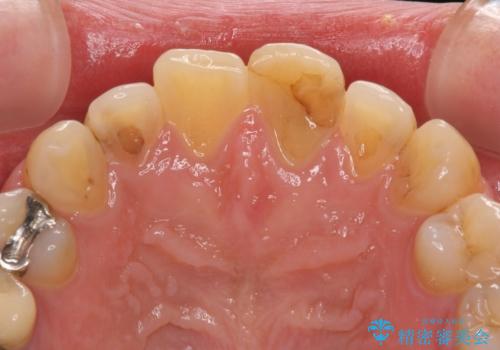

むし歯で神経が取り除かれており、歯の変色と充填材の変色などにより、つぎはぎのような前歯となっていました。

膿の出口も認められたため、まずは根管治療を実施し、オールセラミッククラウンにて補綴治療を行うこととしました。